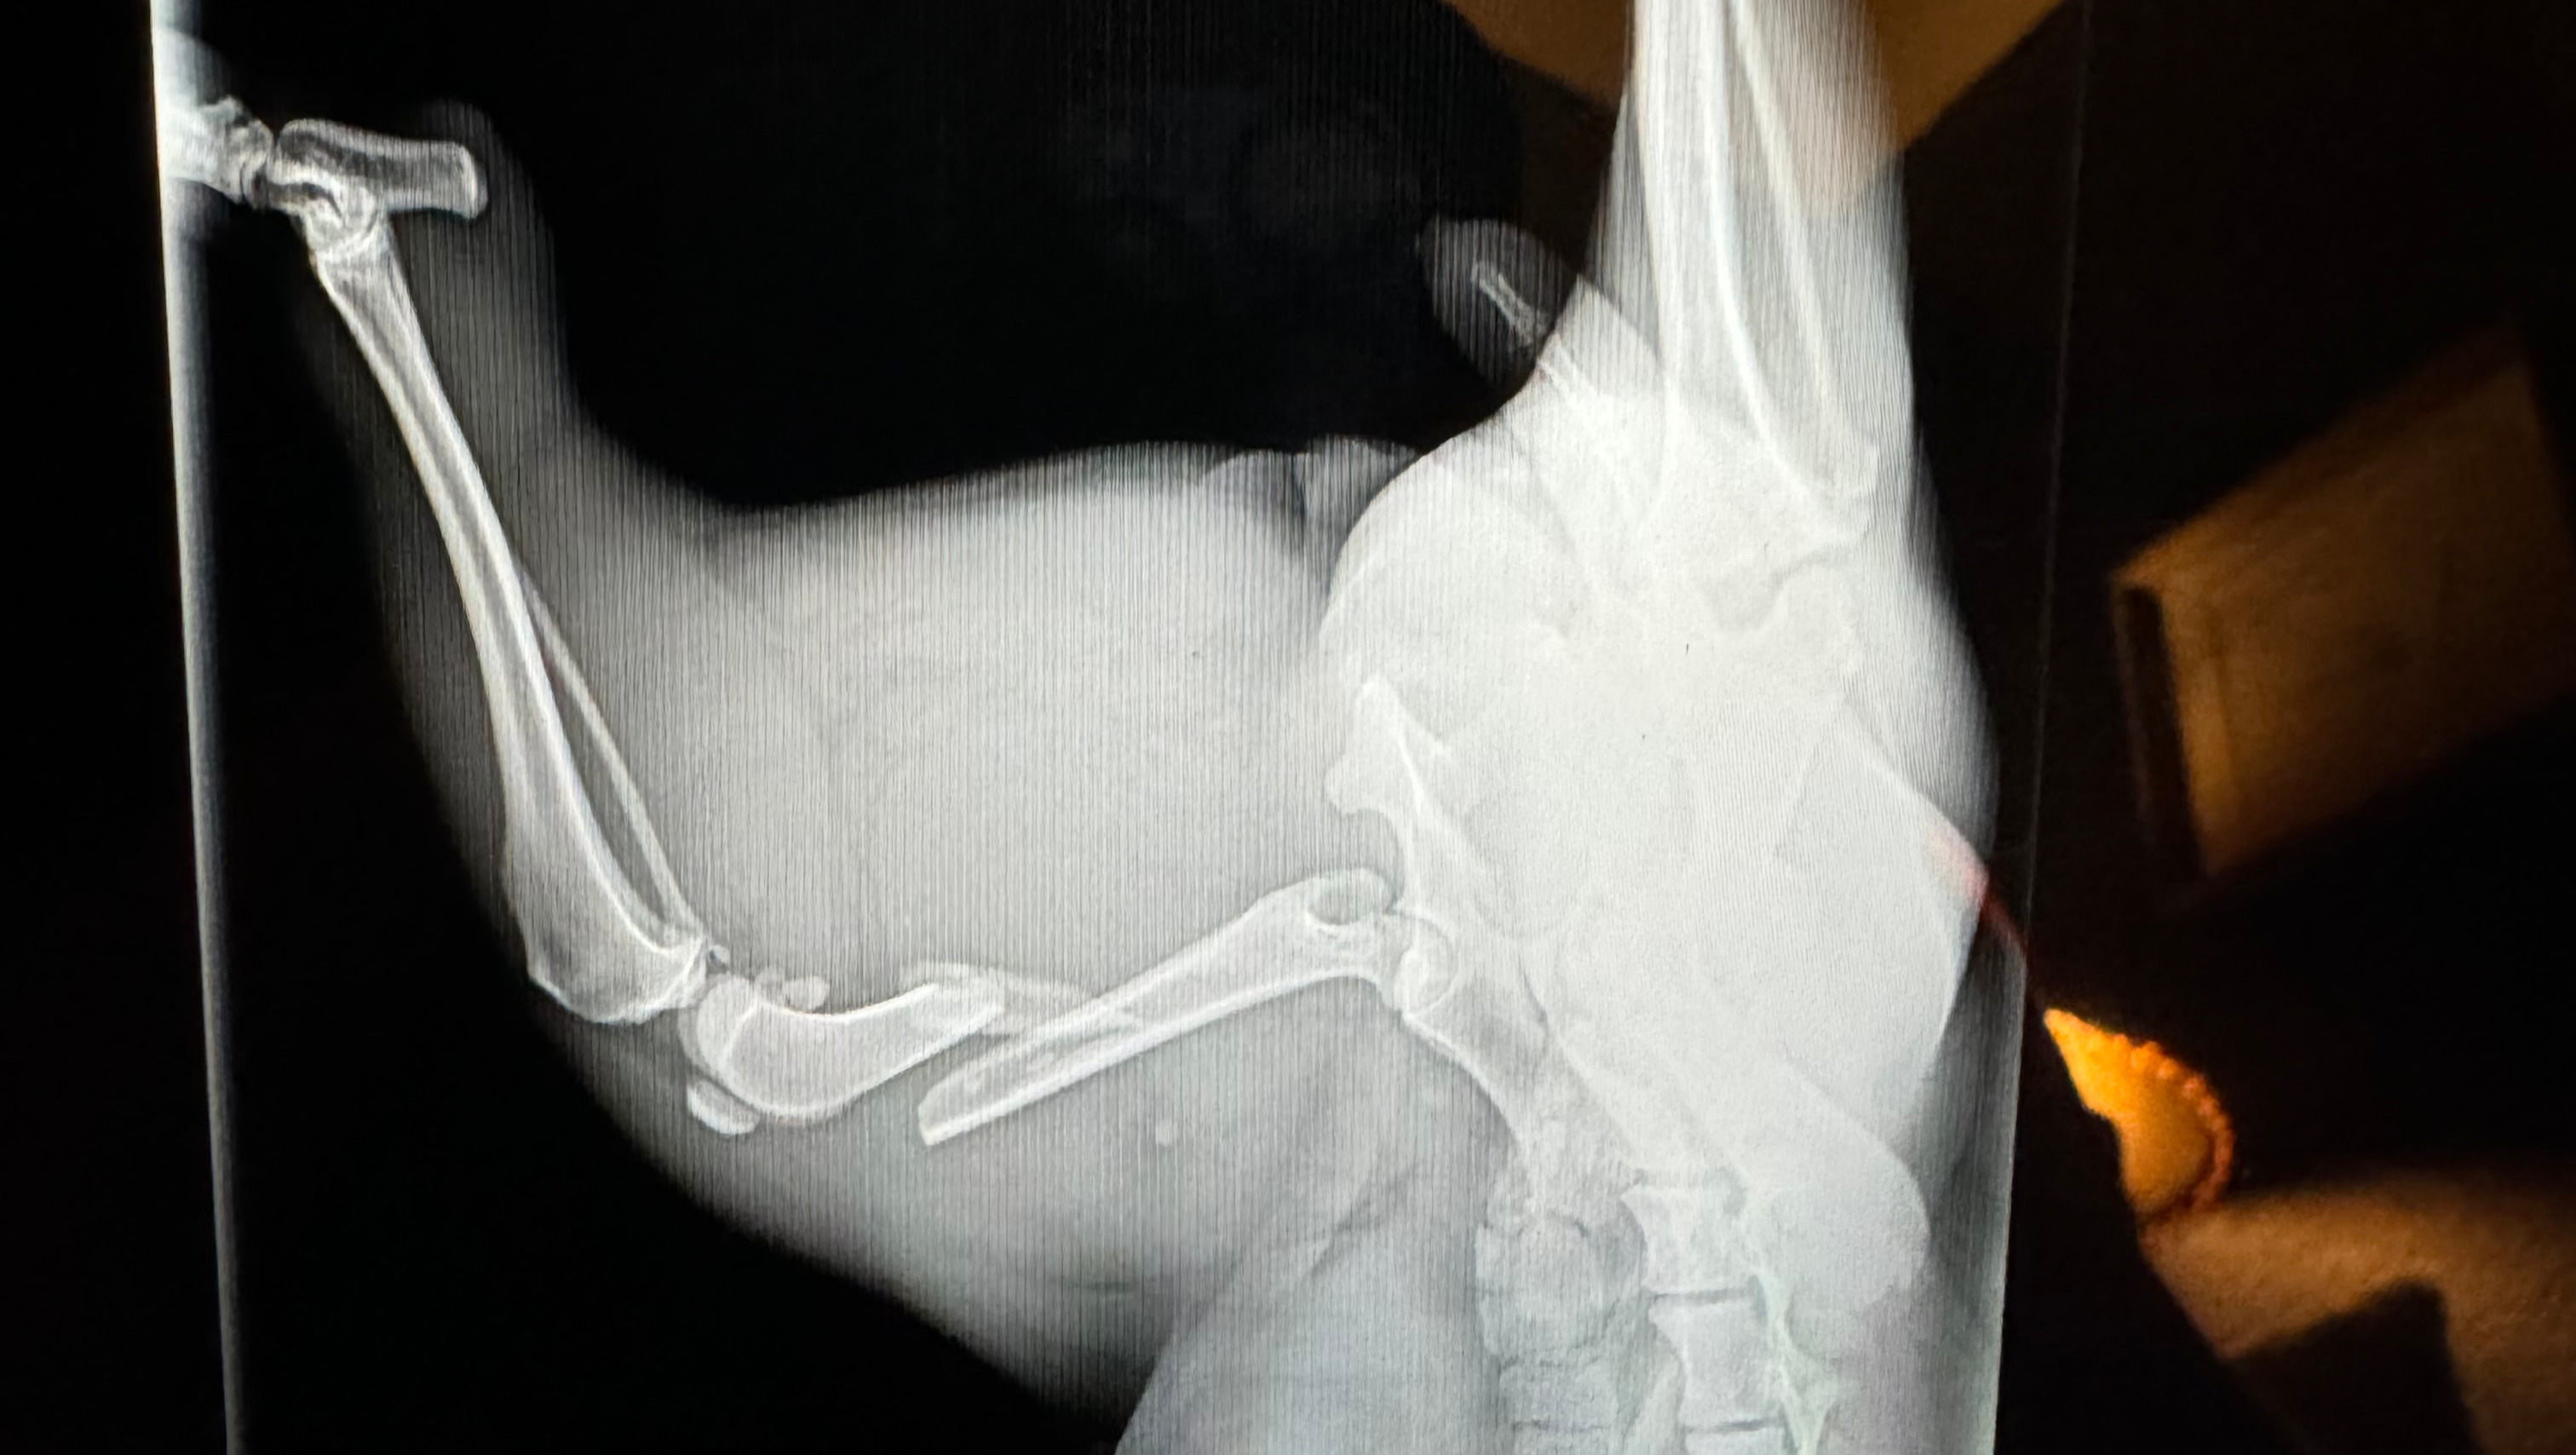

We tried getting her help through the shelter system, but x-rays determined that her fractured femur was too severe for them to handle.

An emergency vet at Kinder4Rescue advised that if she didn't have surgery ASAP she might lose her leg, so we decided to pull her out of the shelter and pay for the surgery ourselves. Luckily, this gentle girl is now recovering after her successful surgery and is home with us.

Surgery to remove pins from femur: $1500